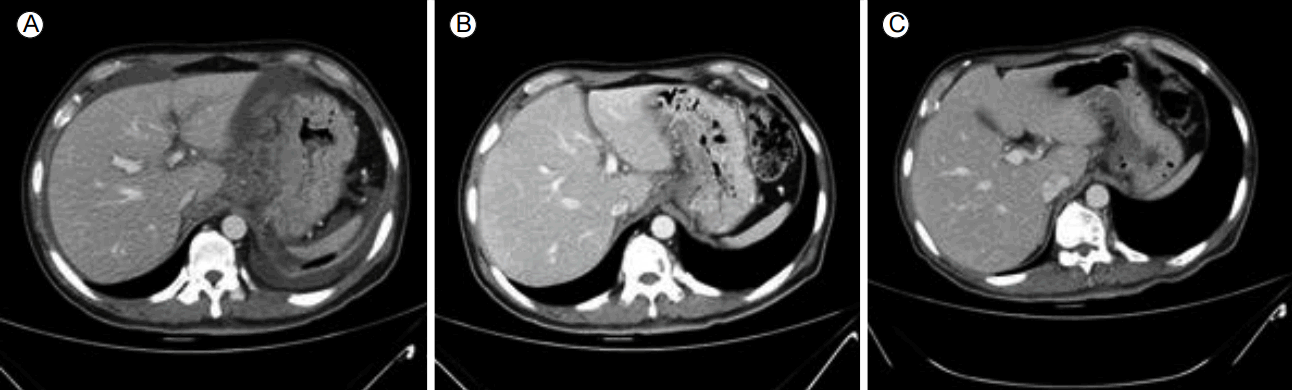

Figure 1.

Enhanced abdomen computed tomography (CT) axial images at baseline (A), after the initial three cycles (B), and additional three cycles (C) of chemotherapy. Baseline CT revealed a bulky mass with extraserosal extension at the gastric body and antrum. After chemotherapy, CT images showed a continuous decrease in the bulky mass.

A 54-year-old male patient was admitted because of tarry stool. Esophagogastroduodenoscopy showed bleeding from a gastric mass, and serial biopsy revealed poorly differentiated adenocarcinoma. A complete blood count showed a hemoglobin of 7.7 g/dL (normal range: 13-17 g/dL), and a laboratory study showed a serum level ALP of 133 IU/L (normal range: 40-129 IU/L). Abdominal CT scan revealed a bulky mass and accompanying extraserosal extension at the gastric body and antrum. The lymph nodes were markedly enlarged at the esophagogastric junction, and in the left gastric, porta hepatis, peripancreatic celiac, superior mesenteric artery, and para-aortic regions, and peritoneal thickening with ascites was evident (Fig. 1A). Positron emission tomography (PET) showed multiple hypermetabolic lymph nodes and hypermetabolic peritoneal thickening in the same lesion was observed on CT. Furthermore, PET revealed extensive hypermetabolic lesions involving the entire spine, sternum, both sides of the rib cage, the clavicle, the scapulae, the humerus and femur, and the pelvic bone. These lesions were identified as multiple bone metastases (Fig. 2). The bone scan showed increased heterogeneous uptake (Fig. 3A).Chemotherapy was planned to treat the cancer. The folinic acid (leucovorin) + fluorouracil (5-FU) + oxaliplatin (eloxatin) (FOLFOX) regimen was administered at 2-week intervals (oxaliplatin, 100 mg/m2 as a 2-h infusion; leucovorin, 400 mg/m2 as a 2-h infusion; and a 5-fluorouracil bolus, 400 mg/m2, followed by a 5-fluorouracil continuous infusion, 1200 mg/m2 in 22 h). After three cycles of chemotherapy, abdominal CT, bone scan, and laboratory tests were performed. Serum ALP was elevated continuously up to 2,038 IU/L, and the bone scan revealed increased intensity of the multiple bone metastases during the same period (Fig. 3B). However, abdominal CT revealed a marked reduction in the primary mass on the gastric body and antrum and nearby lymph nodes, and improvement in the peritoneal cancer (Fig. 1B). We reduced the dose of narcotic analgesics because the patient reported that the bone pain was alleviated throughout his body. Although the bone-scan and serum ALP findings suggested worsening of the bone metastases, we concluded that these findings were the result of the flare phenomenon because the patient’s symptoms and the CT findings indicated that his condition had improved. Accordingly, we continued treatment without changes to the chemotherapy regimen.After three additional cycles of chemotherapy, abdominal CT revealed further reductions in the gastric mass and lymph node metastases (Fig. 1C). A bone scan showed reductions in the intensity and extent of uptake in the multiple bone metastases (Fig. 3C), and the serum ALP level decreased to 510 IU/L (i.e., 1/4 of the previous value), which indicated improvement in the bone metastases. Consequently, the therapy was continued, and the patient received six cycles of FOLFOX without further complications. However, the patient died from hospital-acquired pneumonia when he was admitted for the seventh cycle of FOLFOX.